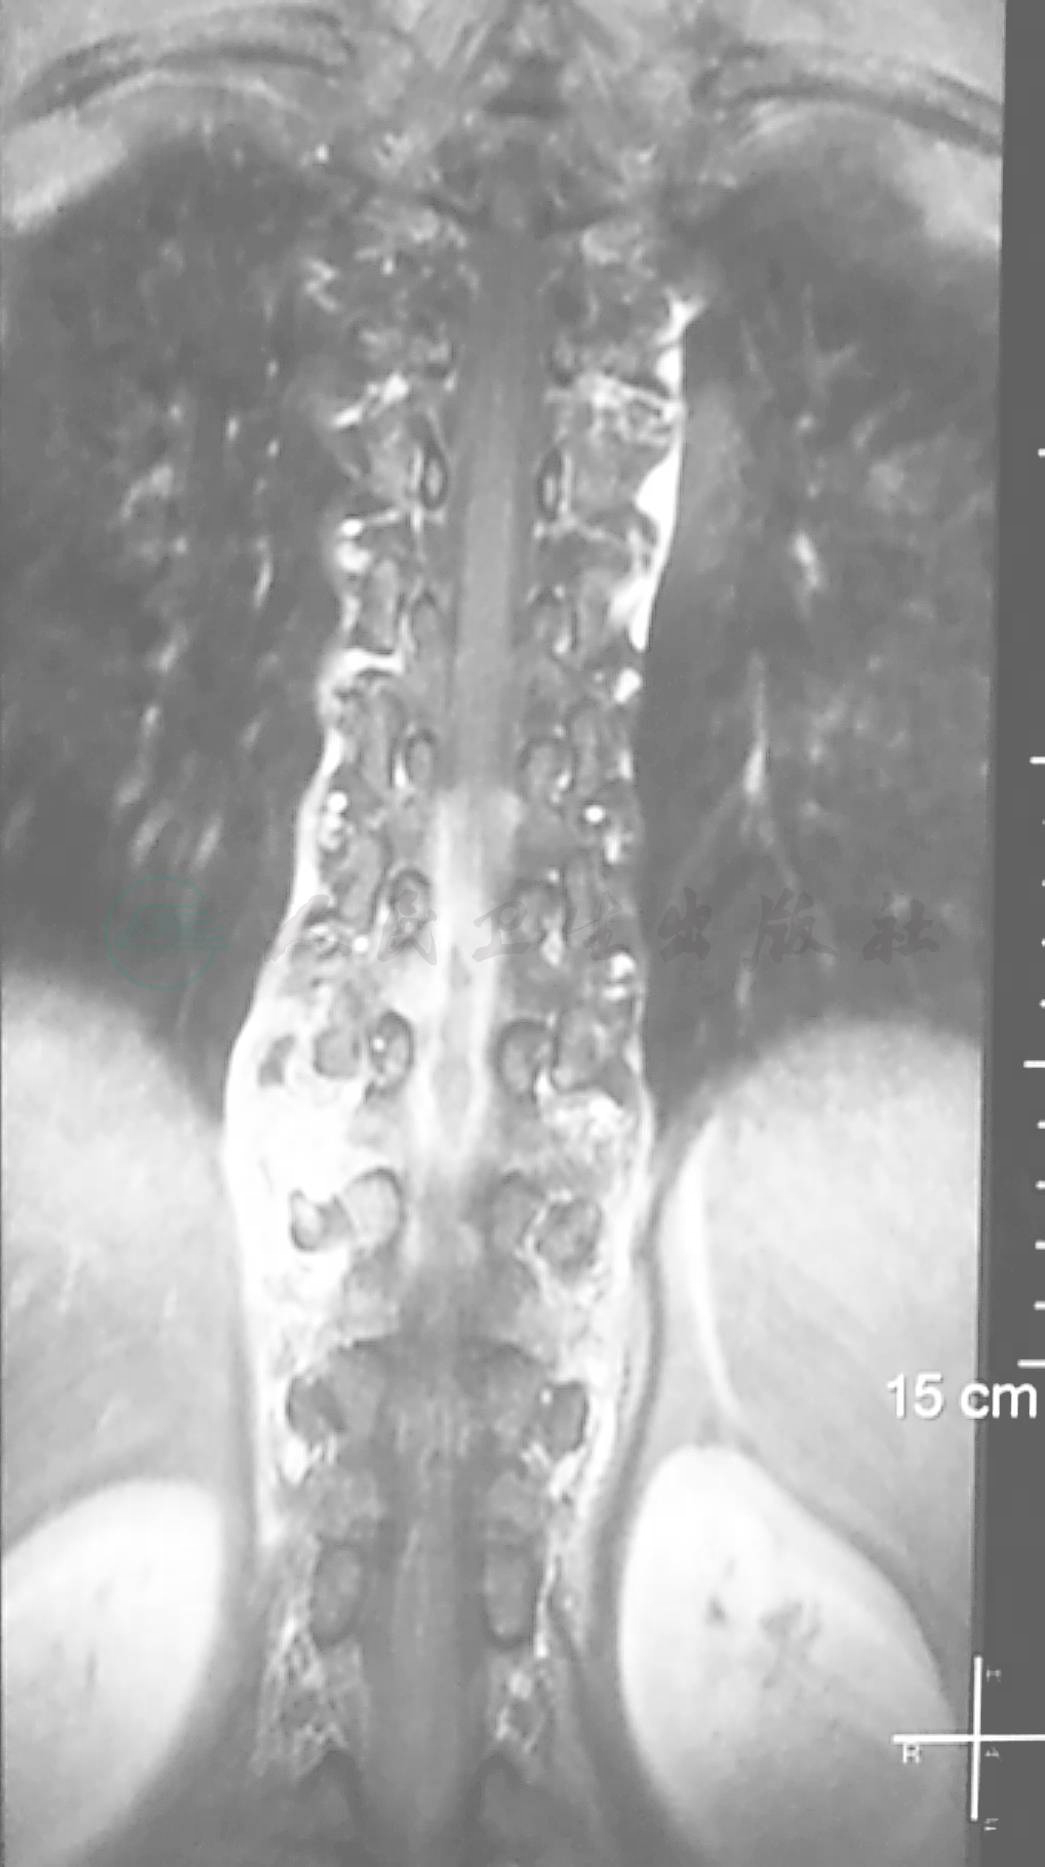

术前磁共振(MRI):可见T8-11占位性病变,T1呈稍低信号,T2呈高信号,强化表现为不均一强化(图1~ 图3)。

图3 术前磁共振(MRI)冠状位

图9 术后磁共振(MRI)强化冠状位